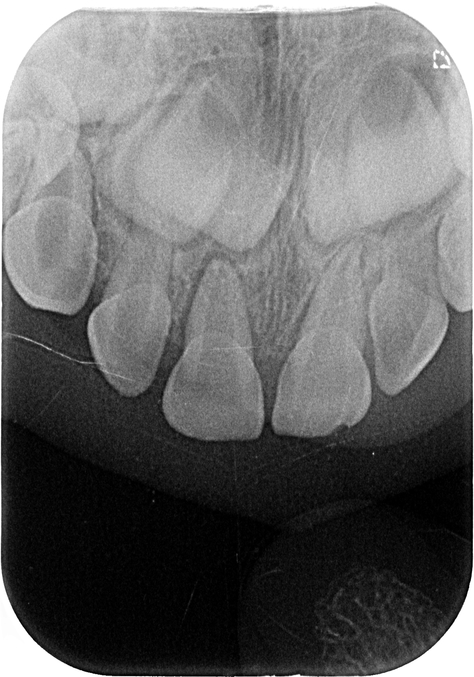

Травма передних зубов - шатается уже 2 недели

откололся зубик Передний зубик темнее других